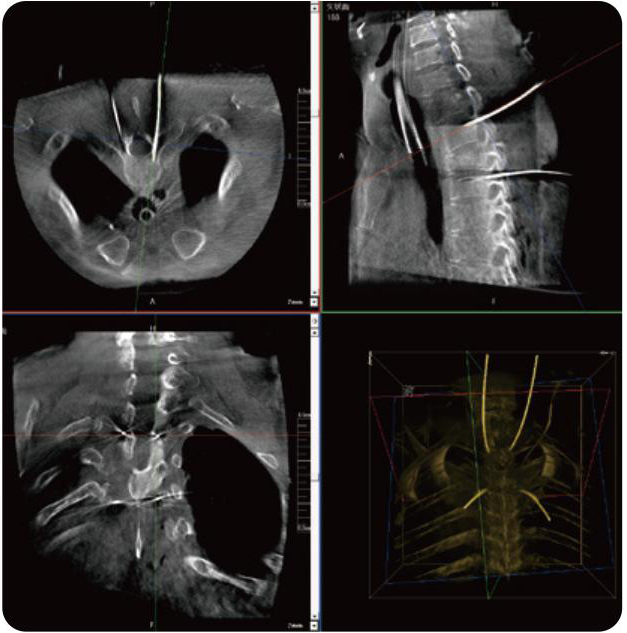

PL300B可應(yīng)用于多節(jié)段脊柱外科手術(shù),輔助醫(yī)生定位病灶部位,為脊柱外科手術(shù)(經(jīng)皮椎體成形術(shù)、椎弓根螺釘內(nèi)固定術(shù)等術(shù)式)提供術(shù)前手術(shù)流程規(guī)劃、入釘位置、角度可視化引導(dǎo),模擬仿真入釘輔助。

PL300B搭配普愛醫(yī)療自主研發(fā)生產(chǎn)的平板3D C形臂,借助一體化自適應(yīng)配準( 軌跡配準)技術(shù),通過追蹤C形臂三維采集軌跡,自動完成圖像坐標建立和系統(tǒng)坐標配準。配準精度更高,操作步驟少,系統(tǒng)運作效率高。